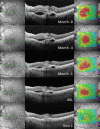

Methods: Patients with recalcitrant nAMD were switched to brolucizumab therapy. Functional and structural parameters 4 weeks after first brolucizumab injection were evaluated including best-corrected visual acuity (BCVA (logMAR)), foveal centre point (FCP (µm)), central subfield retinal thickness (CSRT (µm)) and macular volume (mm³).

Results: Sixty-three eyes of 57 patients with nAMD (52.6% females) with a mean (±SD) age of 79.5±6.7 years were included. Mean change of BCVA was 0.03±0.14 logMAR (p=0.115). Significant reductions were recorded for FCP with a mean (±SD) change of -66.81±72.63 µm, -66.76±60.71 µm for CSRT and -0.27±0.24 mm³ for macular volume (all p<0.001). Intraocular inflammation was observed in seven eyes of seven patients, including one case of retinal vasculitis.